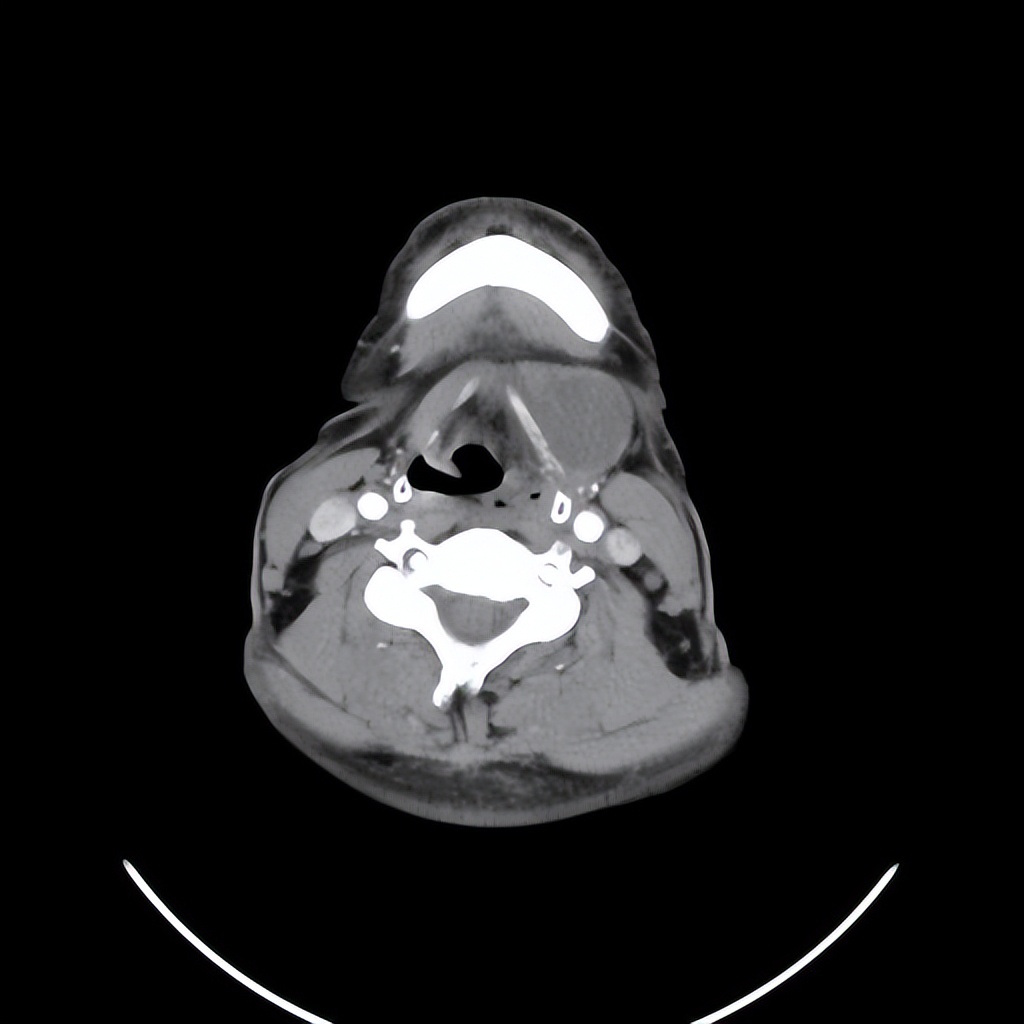

来自广东梅州的管叔,最近发现颈部肿物2周,不痒,不痛,自觉问题不大。但是肿物越来越大了,在家人的劝说下来到佛山复星禅诚医院耳鼻喉做了检查发现是颈部的先天性囊肿。

这个年龄阶段发现颈部的先天性囊肿是比较少见的,一般这种病没有多少的不舒服,但需要做手术切除才可以根治。一般手术早点做效果要好一些,如果囊肿长的比较大了,手术的范围也会相应的扩大,术后恢复就可能会慢一些,手术的风险也会相应的增大。

颈部肿物目前做小切口内镜微创手术比较适合,这样既能切除干净肿物,也会兼顾美观。关于颈部肿物如果您有任何的问题,欢迎留言和耳鼻喉郑立岗医生进一步交流。